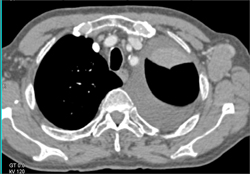

Collaterals in the Chest Wall Shown With Varying Lighting Models